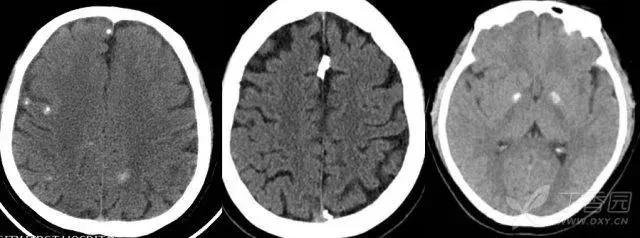

颅内钙化是指大脑中钙质异常沉积的现象。这种现象在CT检查中表现为高密度阴影,通常分为生理性钙化和病理性钙化两种类型。

1. 松果体:这是颅内最常见的生理性钙化之一。值得注意的是,如果钙化的松果体明显偏离中线,或者直径超过10mm,应警惕可能存在的松果体区肿瘤。

2. 脉络膜丛:主要见于侧脑室三角区,通常呈圆形或不规则形,多数情况下为双侧对称性。

3. 大脑镰:多呈沿大脑镰走行的线状,也可局部钙化胶着,呈梭形或球形。

4. 基底节:40岁以上正常人中,颅脑CT扫描时发现基底节钙化也很正常,通常双侧比较对称,但也可不对称,以苍白球钙化最为常见。

5. 小脑齿状核:意义同基底节钙化。